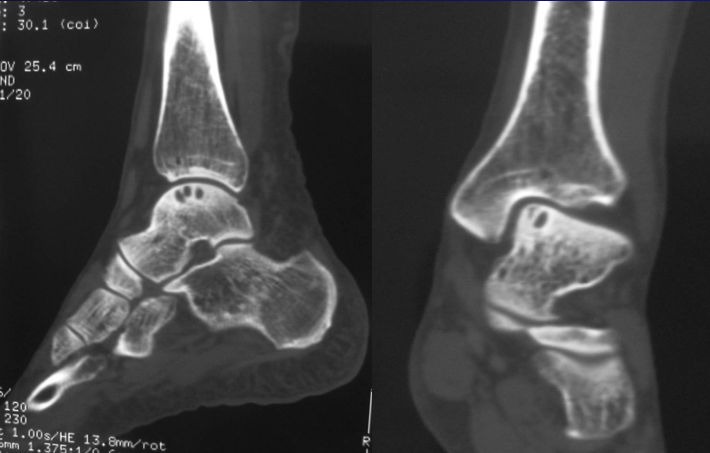

刘建强 男  30岁

软骨退变

游离体形成